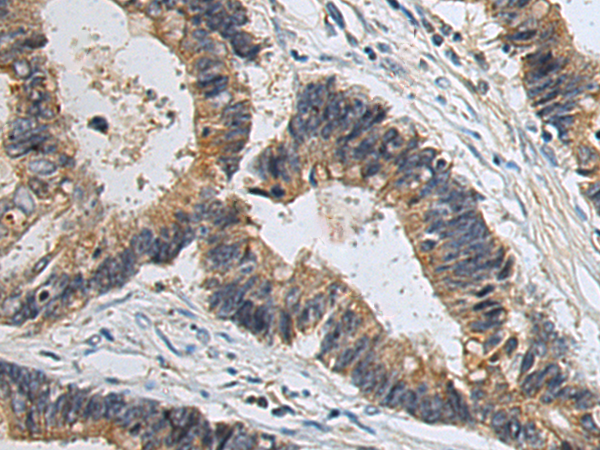

IHC positive control:

Human cervical cancer and Human colorectal cancer

IHC Recommend dilution:

50-100